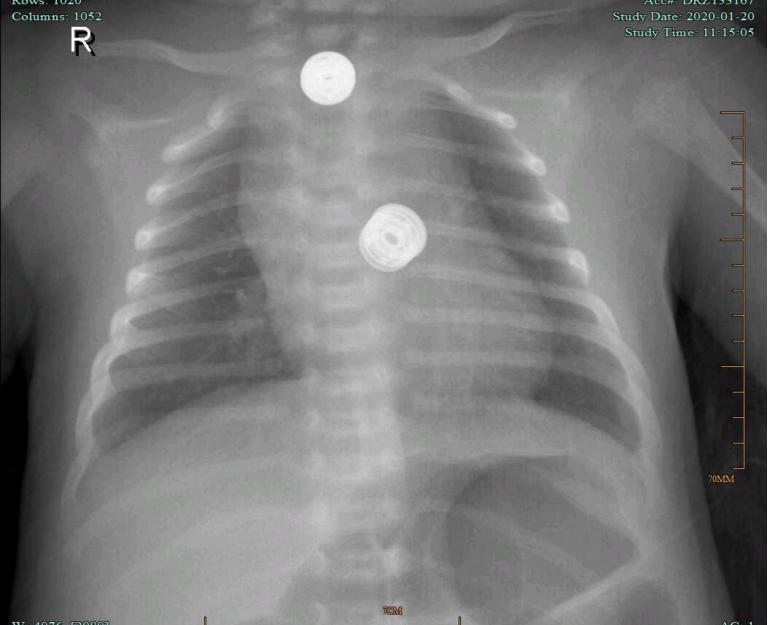

为了明确肺部感染情况给患儿做了肺部X片,结果提示支气管肺炎。完善床边B超检查提示:1、肝脾胰双肾肾上腺区未见明显异;2、头颅扫查未见明显异常。